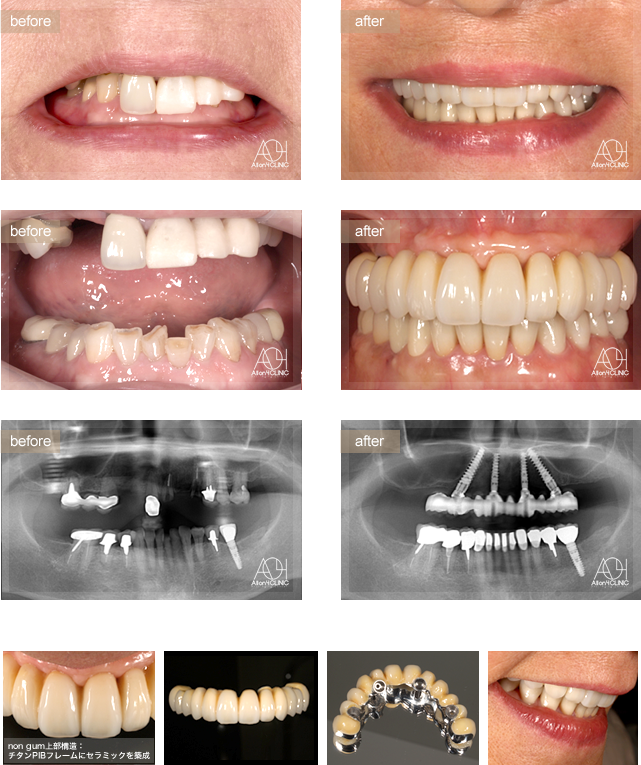

- Maxilla All-on-4,non gum

- All-on-4,non gum

上顎All-on-4 non gumタイプ。上顎上部構造はチタンハイブリッドを採用(チタンPIBフレームにハイブリッドセララミックを築成)。コネクティブティッシュグラフトにより歯肉のマネージメントを行う。